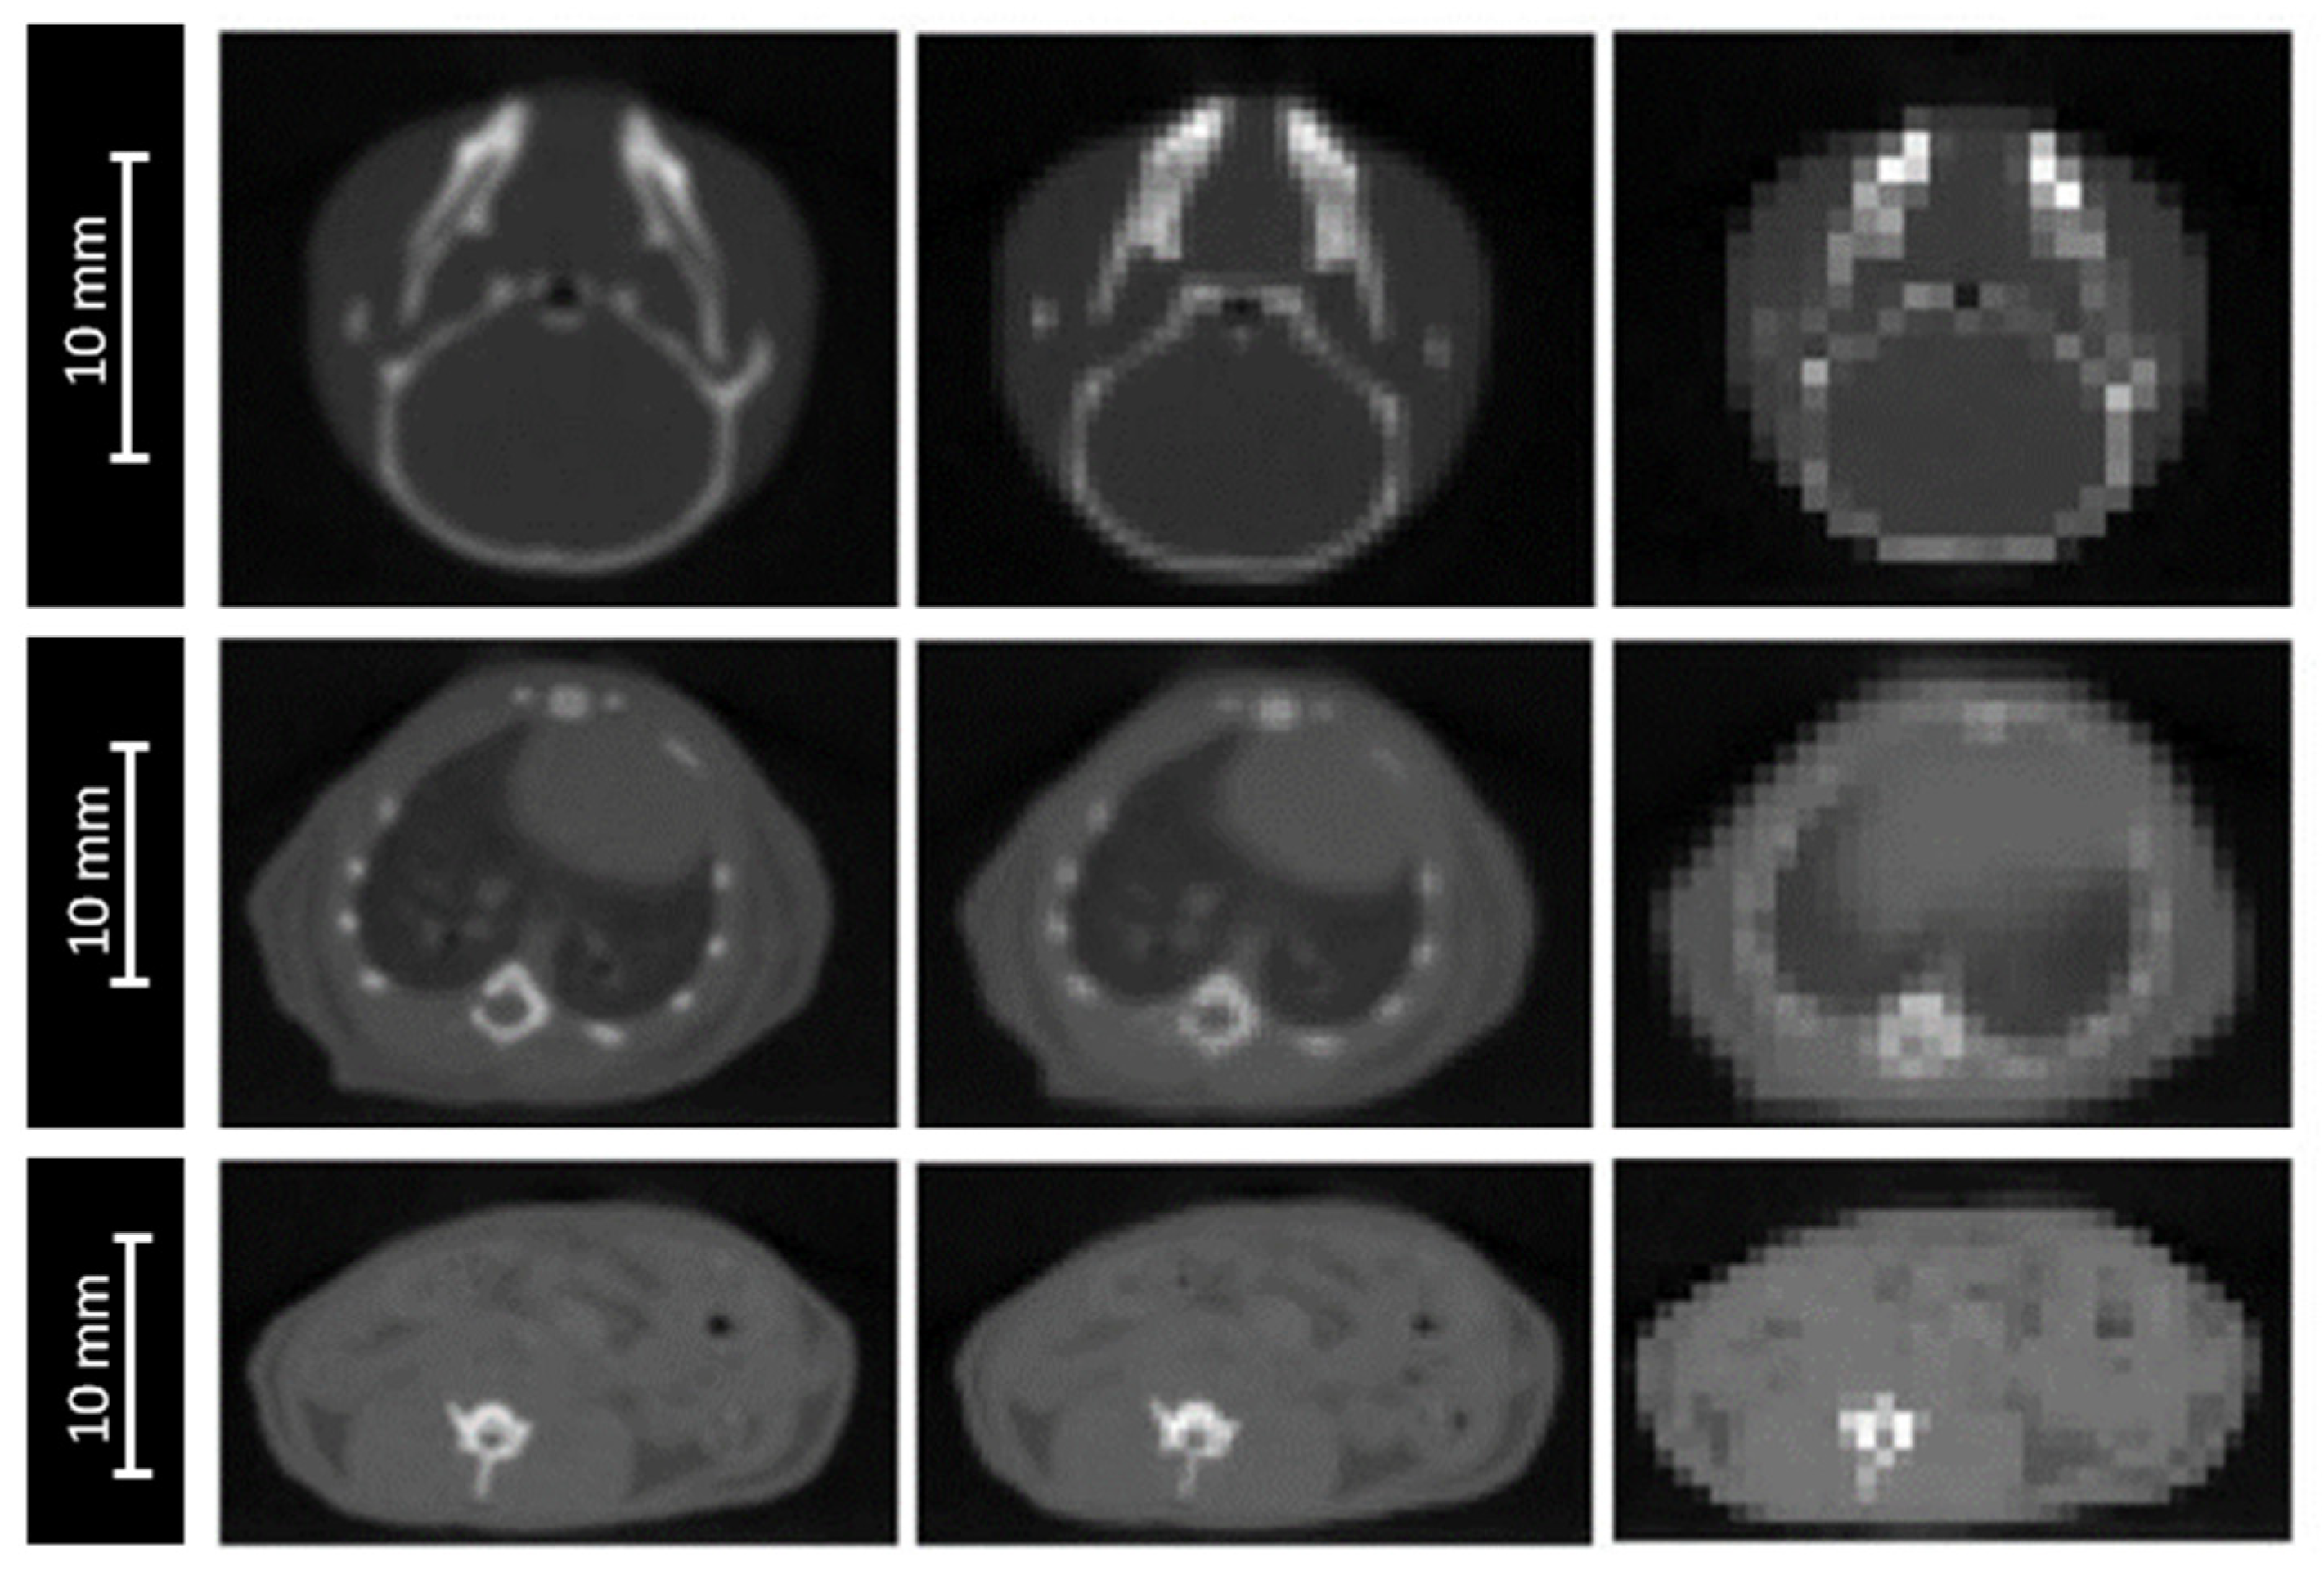

The impact of image resolution was evaluated for brain, lungs and intestine irradiations by degrading the grid size to 0.4 × 0.4 × 0.4 mm3 and 0.8 × 0.8 × 0.8 mm3 (Figure 3), while maintaining the calculation grid size at 0.2 × 0.2 × 0.2 mm3 to prevent the accumulation of sources of uncertainties.

Figure 3.

CBCT of a mouse’s head (top), thorax (middle). and abdomen (bottom) for three different CBCT grid sizes: 0.2 × 0.2 × 0.2 mm3 (left), 0.4 × 0.4 × 0.4 mm3 (middle), and 0.8 × 0.8 × 0.8 mm3 (right).

3.6. CT Grid Size

For the three studied localizations, the CT grid size had no significant impact on the absorbed dose in the plateau. However, the proton range was significantly impacted, with a maximal deviation of ±0.6 mm for the worst spatial resolution (0.8 × 0.8 × 0.8 mm3). The HI98 along the beam axis was not significantly impacted by the degradation of the spatial resolution, excepted from the lungs, for which the HI98 value increased from 0.12 to 0.14, using a spatial resolution of 0.8 × 0.8 × 0.8 mm3. Variations of the HI98 and the Bragg peak position observed for an intermediate spatial resolution of 0.4 × 0.4 × 0.4 mm3 were below the significance thresholds.

The proton range was significantly impacted by the sources of uncertainty related to the dose calculation. This impact stayed low (±0.2 mm) for the biological samples, but reached ±0.7 mm for mice, mainly due to the extreme CBCT grid size degradation of 0.8 × 0.8 × 0.8 mm3. Moreover, this grid size significantly degraded the HI98 along the beam axis. Using a maximal CBCT grid size of 0.4 × 0.4 × 0.4 mm3, the proton range uncertainty could be reduced to ±0.4 mm instead of ±0.7 mm and the HI98 along the beam axis could be preserved. The possible variation of the energy spread of the beam had no impact for an irradiation in the plateau. However, we observed a major impact of the peak height and width (Figure 4). This point will be critical for irradiation in the Bragg peak or in the spread-out Bragg peak. An additional study will have to be carried out to estimate the uncertainty in this context [4].